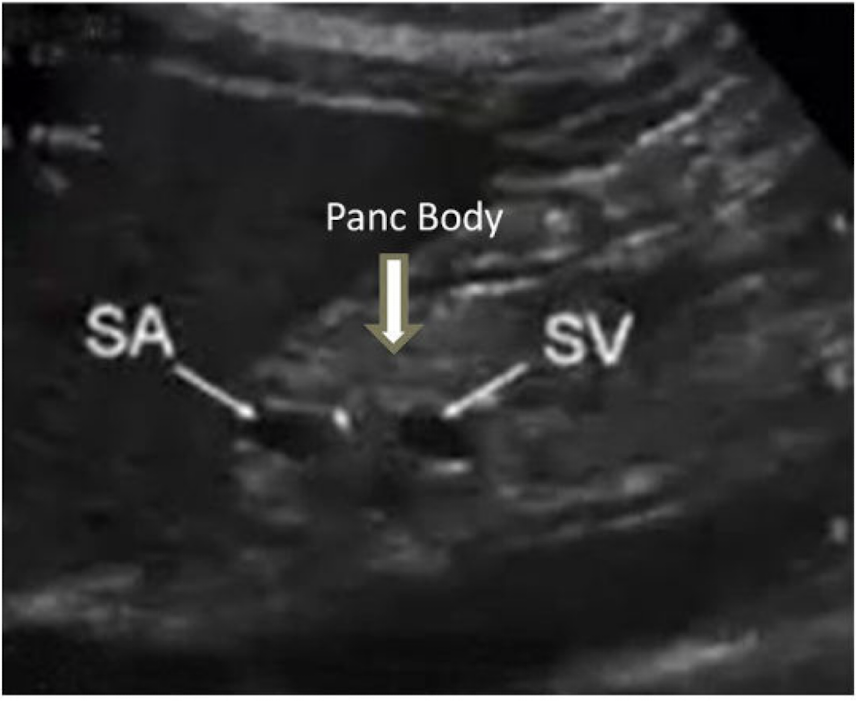

Where was this image taken from?

Shows sagittal pancreatic body more towards patients left

What is this image showing?

Sagittal pancreatic tail